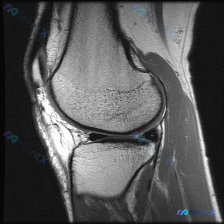

刚看到这个膝关节MRI读片的病例,整理一下完整的病例信息和分析思路,和大家讨论一下这种情况的处理。 病例基础信息 本次提供的是单幅膝关节矢状位T1加权MRI影像,核心疑问是评估是否存在半月板异常。 影像学观察结果 我们先按解剖结构整理观察结果: 1. 骨骼结构:股骨远端、胫骨近端、髌骨骨皮质连续,骨...

刚整理了一份有意思的影像读片病例,和大家分享一下思路。 病例基本信息 本次仅提供放射影像-膝盖MRI-T1序列-矢状位单张图像,核心问题是询问图像中是否存在半月板异常。 影像学读片结果 我仔细读了这张片子,所有结构的情况如下: 1. 骨骼结构:股骨远端、胫骨近端、髌骨的骨皮质连续,骨髓信号正常,没有...

病例读片:主诉半月板异常,但这张MRI没看到明显问题? 整理了一份有意思的膝关节MRI读片病例,核心矛盾是临床提示半月板异常,但单张影像没找到对应病变,分享一下分析思路。 --- 病例基本影像信息 这是一张膝关节矢状位MRI单张切片,不是用户最初提到的肘部影像。 影像基础评估 - 定位:膝关节矢状位...

看到这个病例挺有代表性,整理了完整的分析思路分享给大家。 病例与影像基础信息 这是一份单张膝关节矢状位MRI影像,临床关注点是"半月板异常",需要基于现有影像做分析。 影像的核心征象整理如下: 1. 序列与定位:膝关节中部偏内侧矢状位,考虑为PDWI或T1加权像,适合显示半月板、韧带解剖结构 2....

刚整理了一份很有临床参考意义的病例读片资料,分享一下思路,大家一起讨论。 病例基本信息 临床关注点:患者自述/临床怀疑存在半月板异常,提供单张膝关节MRI T1序列矢状位图像供分析。 影像读片结果 先把读片的核心结果整理出来: 1. 图像与解剖:图像对比度良好,为膝关节矢状位T1序列,可清晰显示股骨...

看到一个很典型的临床-影像矛盾病例,整理出来和大家分享思路。 病例核心信息 这是一张膝关节矢状位MRI单张图像,临床关注点为「半月板异常」,我们先来看影像的全面评估结果: 1. 骨骼结构:股骨远端、胫骨近端、髌骨轮廓完整,无明显骨皮质中断或骨折 2. 关节软骨:股骨、胫骨关节面软骨信号均匀,无明显剥...